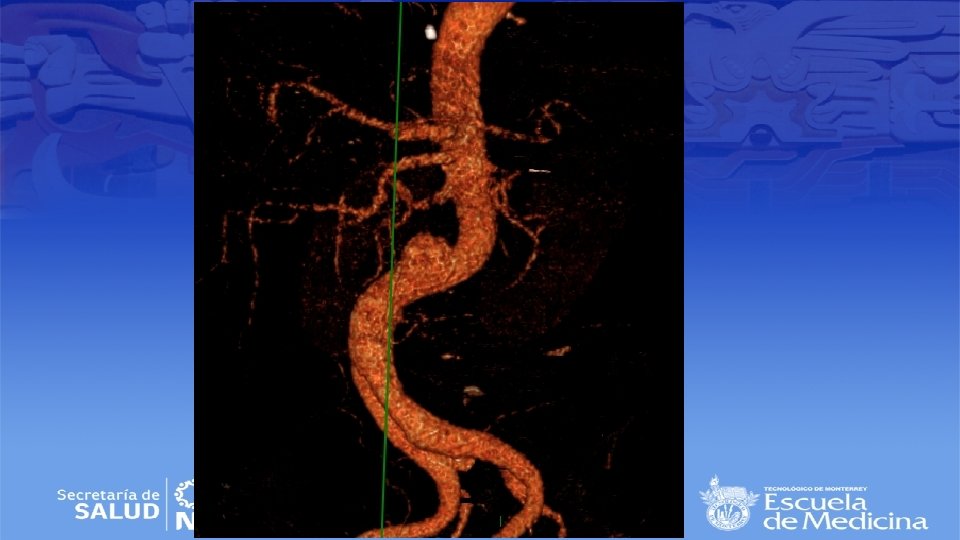

Angiotac

Impresión Diagnóstica • IDX: Aneurisma Poplíteo bilateral

Tamizaje • Aneurisma poplíteo único tiene un riesgo de presentar aneurisma abdominal en 40% de los casos • Aneurisma Bilateral hasta en un 70% de los casos • Guías Clínicas – Masculinos con tabaquismo + en edades de 65 -75 años – Femeninas con antecedentes familiares de aneurismas

Condiciones Anatómicas • Continuidad de la arteria femoral superficial • Aneurismas verdaderos • Fusiformes o saculares